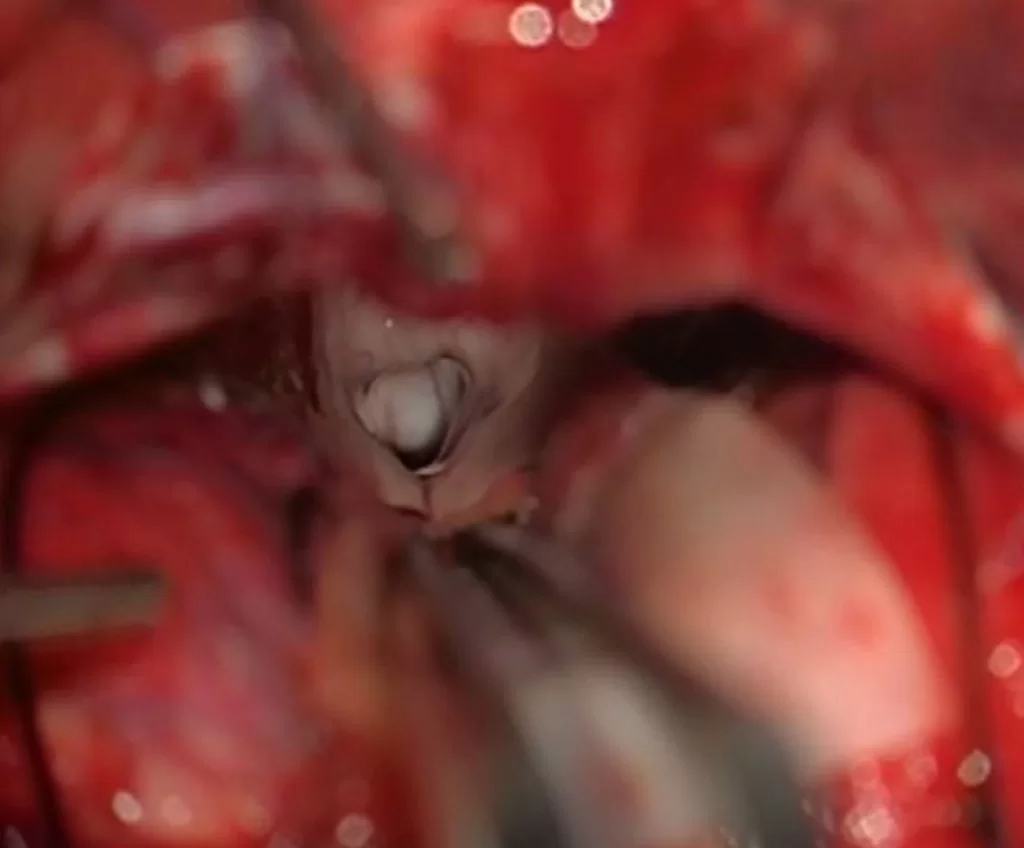

Διενεργήθη υποσκηνιδιακή υπερπαρεγκεφαλιδική προσπέλαση και ολική εξαίρεση της βλάβης.

Οι όγκοι της περιοχής του κωναρίου ή αλλιώς όγκοι στην περιοχή της επίφυσης είναι χειρουργικές προκλήσεις λόγω της θέσης του όγκου (ουσιαστικά στο «κέντρο» του εγκεφάλου) αλλά και λόγω της στενής σχέσης τους με σημαντικές ανατομικές δομές όπως πχ. οι εν’ τω βάθει εγκεφαλικές φλέβες και το τετράδυμο πέταλο.

Η συγκεκριμένη ασθενής χειρουργήθηκε σε καθιστή θέση. Η καθιστή θέση προσφέρει κάποια πλεονεκτήματα όμως είναι εργώδης για τον χειρουργό και απαιτεί συγκεκριμένη αναισθησιολογική προετοιμασία και υποστήριξη.